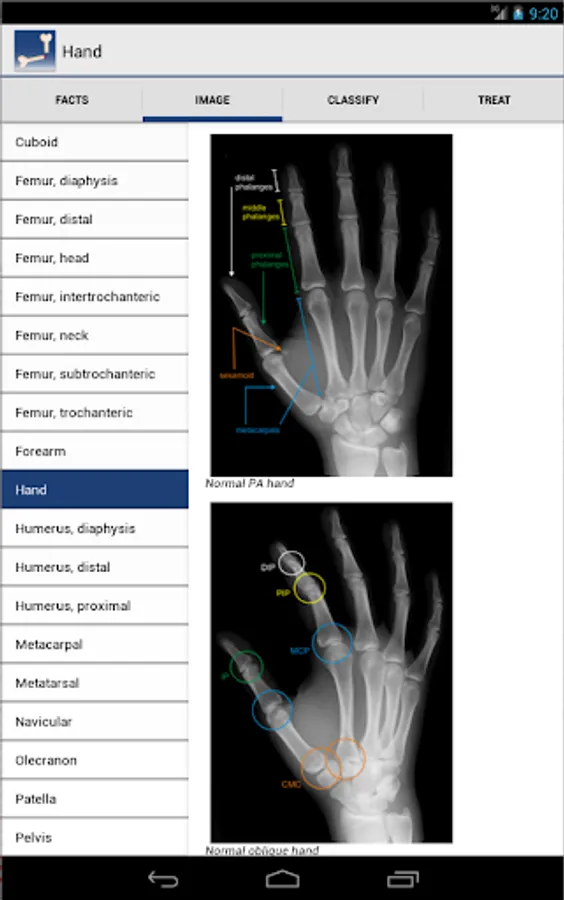

Ortho Traumapedia is designed to provide quick access to information important to the treatment of adult skeletal trauma. Based on extensive literature review, Ortho Traumapedia compiles the current standard of care in a high-yield, easy to use format including dozens of original images to help visualize fracture patterns and radiologic findings.

Imaging begins with the standard radiographic examinations for each anatomic region. This is followed by injury-specific views, relevant metrics and findings as well as supplemental modalities.